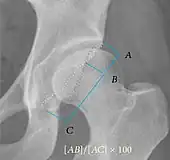

| Femoral head-neck offset | ![]() |

Offset of the femoral head with regard to most prominent aspect of the femora neck | >10 mm |

| Offset percentage | Femoral head-neck offset related to femoral head diameter | >0.18

| |